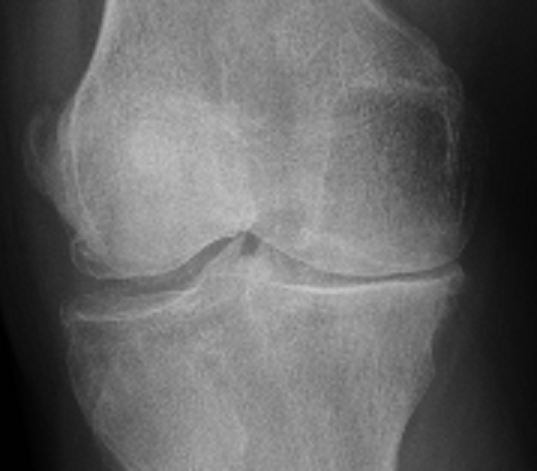

Los implantes de oro periarticulares actúan en las partes blandas de la articulación y es claro el beneficio clínico que se obtiene. Pero hasta ahora no se había objetivado el rol de los implantes a nivel del cartílago hialino en pacientes humanos. A continuación se observan las RX de un paciente octogenario con gonartrosis bilateral y genu varo tras dieciocho (18) meses de colocación de implantes. La buena evolución clínica es paralela a los cambios radiológicos que se observan especialmente en la articulación tibiofemoral interna en donde la degradación cartilaginosa es mayor. Se comparan las radiografías anteriores y posteriores a los implantes, con un aumento significativo de la interlínea articular.